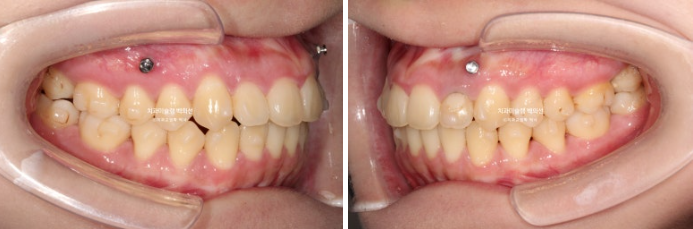

23.12~25.08

반대교합의 개선이 됩니다.